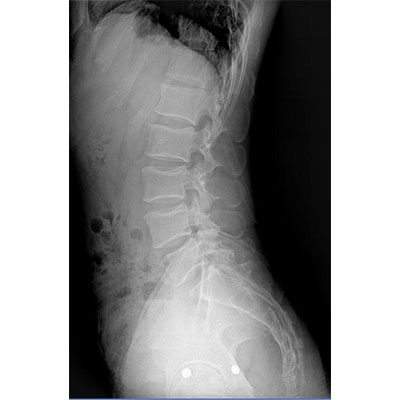

● 采用自主研發(fā)的技術(shù),在保證優(yōu)質(zhì)圖像的前提下,大大降低X射線劑量,用心呵護醫(yī)護工作者及患者的健康。

● 短曝光時間,便于老年人、兒童、殘疾人進行臨床拍攝。避免這類群體因不能有效控制身體運動等因素造成的運動偽影,提高攝片質(zhì)量及效率。